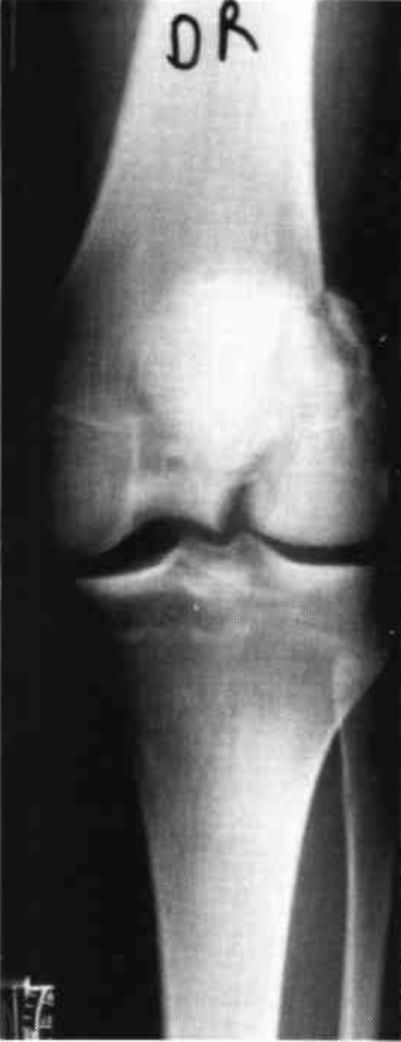

A nineteen year old male sustained a distal fracture with a split condylar fracture to the right leg (Fig. 10) and a lateral condyle fracture on the contralateral side (Fig. 11). Fractures were stabilized, but were not internally fixed at time of admission because of emergency vascular repairs being required. Three days post injury, the patient underwent ORIF of his fractures (Fig. 12 and Fig. 13). The right leg was placed in a free knee Mobilizing Brace and the left leg was placed in the rehabilitative free knee orthosis. A continuous passive motion dynamic suspension system was placed on the lower right extremity (Fig. 14). The lower left extremity had normal pain free motion following surgery. The patient was kept in passive motion for five days and achieved 0-100° of pain free motion. A cast brace was applied on the right extremity; the patient received gait training and was discharged.

Figure 10:

Figure 11: